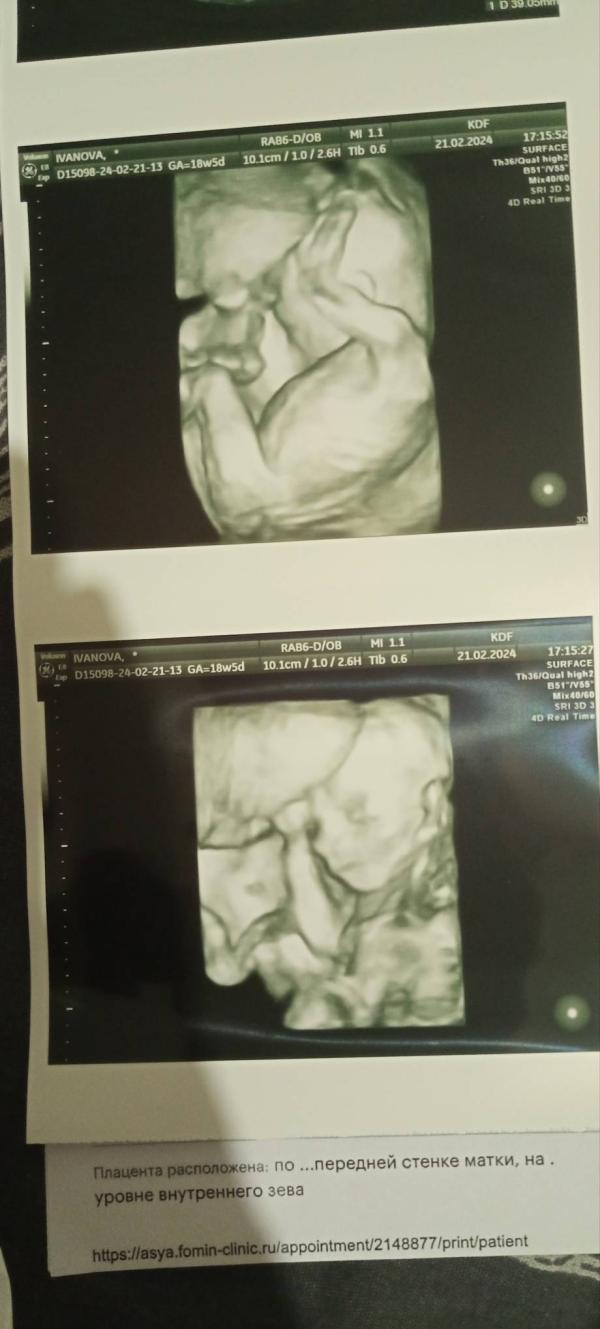

Как же быстро пролетело время))))) Казалось вот только узнала что беременна, а уже бусинка рядом сопит)))) Наслаждайтесь каждым моментом беременности!!! Самое главное не накручивайте себя, если чтото беспокоит сразу к врачу!!!! Сколько помню врача узи просто достала, что не так сразу к ней😝😝😝